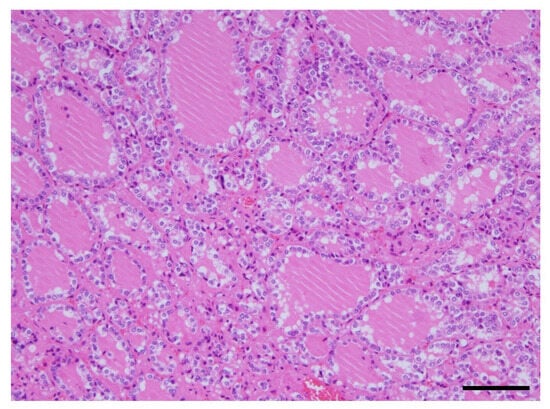

A Case of Giant Goiter Associated with Airway Stenosis Caused by Long-Term Intravenous Epoprostenol Therapy for Idiopathic Pulmonary Arterial Hypertension

Nishiura, K.; Nakazato, K.; Yokokawa, T.; Suzuki, Y.; Kurosawa, Y.; Wada, K.; Shimizu, T.; Oikawa, M.; Kobayashi, A.; Sugimoto, K.; et al. A Case of Giant Goiter Associated with Airway Stenosis Caused by Long-Term Intravenous Epoprostenol Therapy for Idiopathic Pulmonary Arterial Hypertension. J. Clin. Med. 2023, 12, 6359. https://doi.org/10.3390/jcm12196359